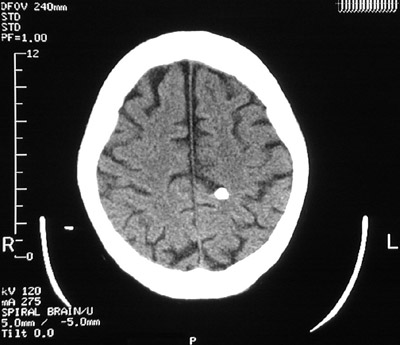

| A bright, rounded lesion is seen in the medial left frontal lobe above. This is a calcifying cysticercus cyst. The organism eventually dies and there can be an inflammatory reaction followed by dystrophic calcification. These lesions may be multiple, as is apparent in the two views below. |